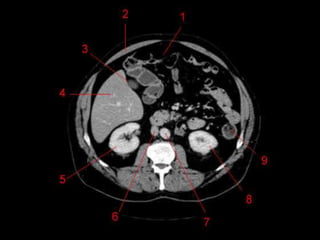

Vasos Hepáticos

• Veia porta

– Formada pela união da Veia Esplênica e Mesentérica

Superior

• Artéria Hepática

– Segmento da Tronco Celíaco

– Dividida em Comum e Própria pelo surgimento da artéria

gastroduodenal.

• Na maioria das pessoas, a artéria é anterior a veia

(91%). Na maioria das pessoas, a artéria hepática

direita passa atrás do ducto hepático comum. (64%)

Vasos Hepáticos • Veiaporta – Formada pela união da Veia Esplênica e Mesentérica Superior • Artéria Hepática – Segmento da Tronco Celíaco – Dividida em Comum e Própria pelo surgimento da artéria gastroduodenal. • Na maioria das pessoas, a artéria é anterior a veia (91%). Na maioria das pessoas, a artéria hepática direita passa atrás do ducto hepático comum. (64%)